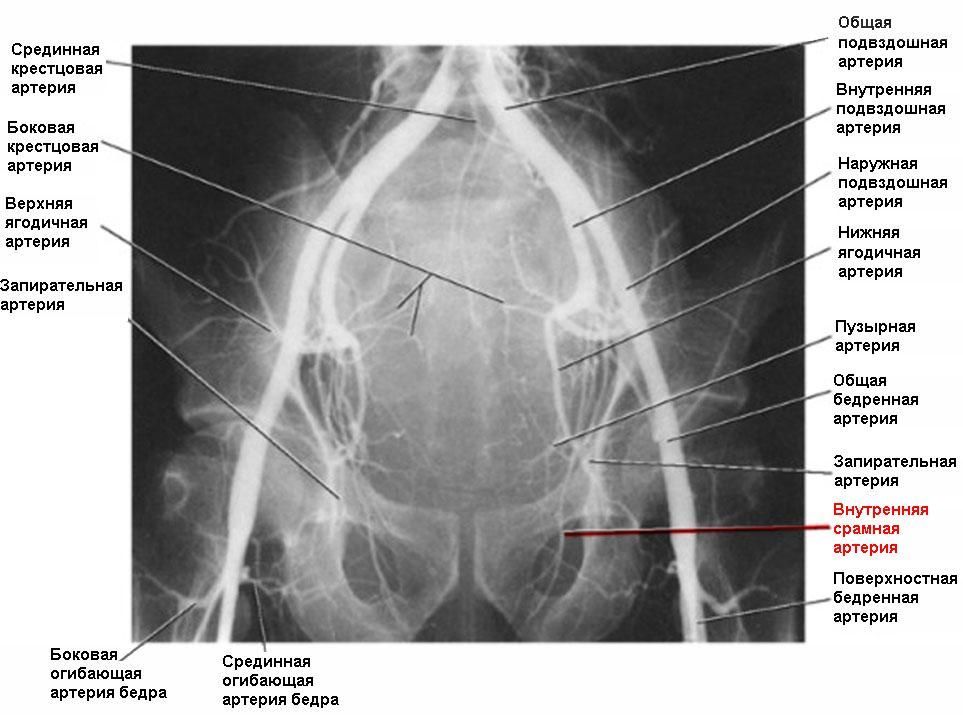

После физической и психоэмоциональной стимуляции нервы посылают сигнал к СОСУДИСТОЙ системе, что значительно увеличивает приток крови к половому члену. Две артерии несут кровь в кавернозные тела полового члена и после кровенаполнения и увеличения давления в кавернозных телах полового члена происходит эрекция.

В 80% случаев причина носит СОСУДИСТЫЙ характер. Как было объяснено выше, в случае нарушения притока крови к половому члену, НАСТУПАЕТ ЭРЕКТИЛЬНАЯ ДИСФУНКЦИЯ. Основной причиной снижения притока крови служит сужение просвета приводящих артерии в результате атеросклеротического процесса в стенке артерии.

Если причиной эректильной дисфункции является недостаточный приток крови по артериям в половой член, то диагноз ставиться на основании специального исследования этих артерии – АНГИОГРАФИИ. В случае наличия сужений или закупорок в приводящих артериях, они четко видны на ангиограммах.

Мы исходим из фундаментального правила – устранить причину, а не лечить косвенным путем, как, например, действуют общеизвестные лекарства Виагра или Сиалис. В нашей клинике мы предлагаем современную и высококвалифицированную диагностику сосудистой системы таза и гениталий и, в случае наличия показаний (сужения или закупорки артерии), мы устраняем эту причину с помощью малоинвазивного (без хирургической операции) лечения – расширения суженных артерии и их внутрипросветного протезирования.